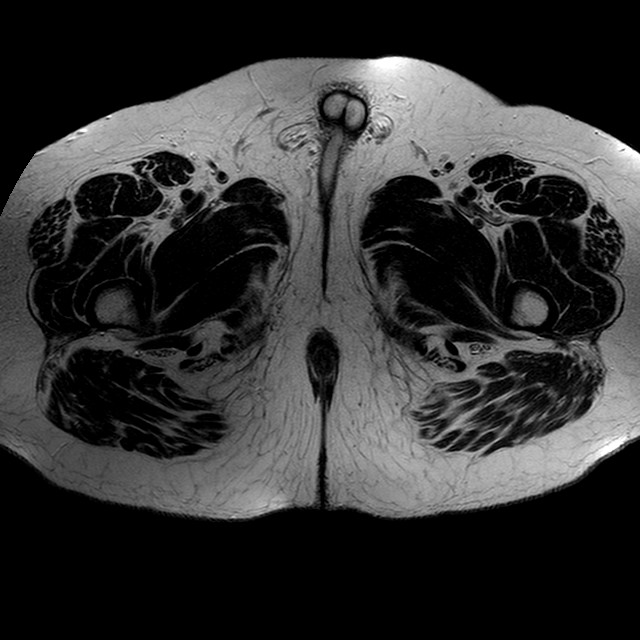

Esami: RMN BACINO

T2w TSE

Evidenti e simmetriche alterazioni osteofitosiche in regione coxo femorale con riduzione delle rime articolari. Degenerazione completa del cercine glenoideo. Non attuali segni di versamento articolare. Non segni di edema osseo che escludono attuale algodistrofia od osteonecrosi. Lieve e simmetrica riduzione del trofismo della muscolatura glutea.